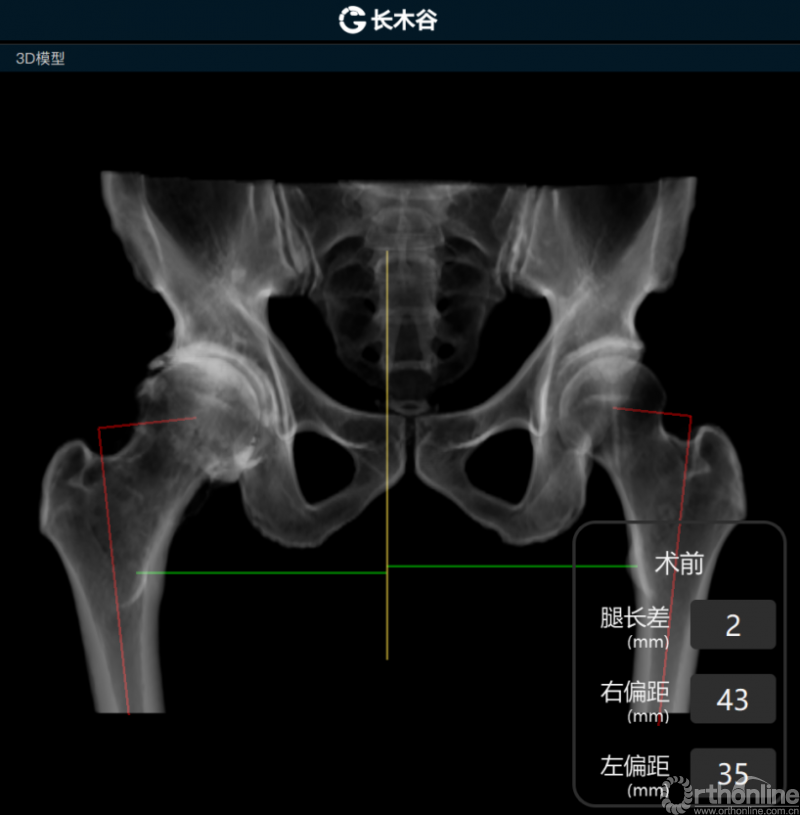

AI HIP系统对患者术前偏距与腿长差进行智能测量与评估

而后,由人工智能判断患者双侧腿长差及股骨偏心距大小,如图可见,由于长期受到的髋关节撞击征影响,该患者术前腿长差为2mm,右侧股骨偏心距为43mm,明显大于左侧股骨偏心距35mm。

AI HIP系统智能安放54mm直径的强生Pinnalce髋臼杯

最后,AI HIP系统根据患侧股骨颈干角、偏心距偏大的特殊情况,智能选择使用高偏高颈干角假体,对下肢等长和等偏心距重建做出了精准设计。根据系统预测结果,术中使用54mm Pinnalce髋臼杯、12号CORAIL高偏股骨柄、36mm 陶瓷股骨头、小转子上23mm截骨,实现髋关节的个体化、精准化重建。